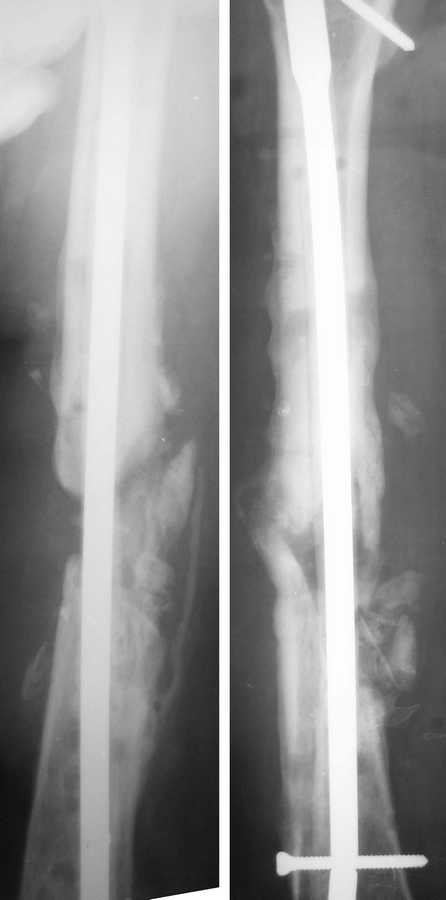

Две недели назад Павел Иванов любезно приехал в нашу больничку и прооперировал пациентку.Сначала разрезом около 10 см вскрыли зону ложного сустава. Мощные рубцы, отсутствие инфекционных очагов. Особо углубляться не стали, ушили рану, выполнили остеосинтез стержнем, предварительно покрыв его цементом с антибиотиками.Послеоперационные снимки - в приложении.

Из вариаций на ту же тему - недавно был в ЦРБ г. Almada (Португалия), где шеф травматологического отделения знакомый многим Nuno C. Lopes. Они там использют гвозди не покрытые, а заполненные цементом с антибиотиком. Для выхода антибиотика наружу в гвозде сделаны не очень многочисленные отверстия. Картинка в приложении.

С одной стороны, концентрация антибиотика вокруг явно меньше, с другой - выходит наружу дольше, и гвоздь можно взять толще. Отмечают частые

обострения инфекции после имплантации, но вскоре они затихают.